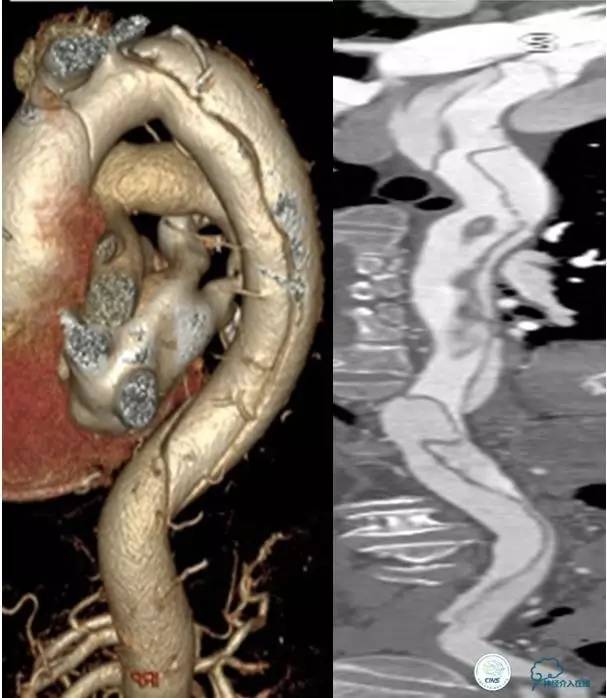

治疗原则:急查主动脉CT。

▼主动脉全程CT

中间诊断:

主动脉夹层 De Bakey Ⅰ型

脑梗死

治疗原则:

继续监测血流动力学指标

绝对卧床、控制血压、强效镇静与镇痛

急请血管外科会诊